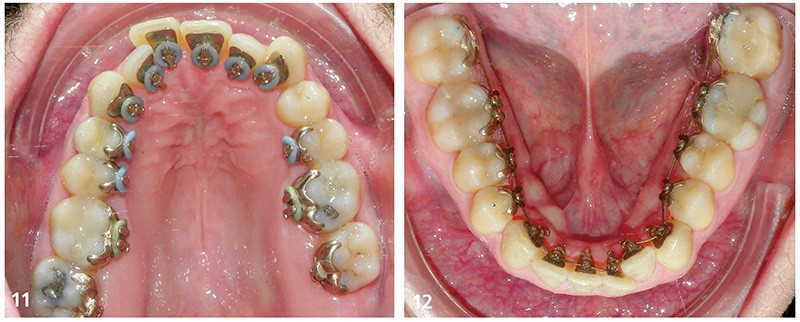

Sur la radiographie panoramique (fig. 9) le bilan dentaire est normal et le parodonte est sain, il existe des images péri-apicales au niveau des 36 et 37, les traitements canalaires semblent de qualité. Sur la téléradiographie du crâne de profil (fig. 10) il n’existe pas d’anomalie du sens sagittal, le sens vertical est normodivergent avec des axes incisifs corrects.